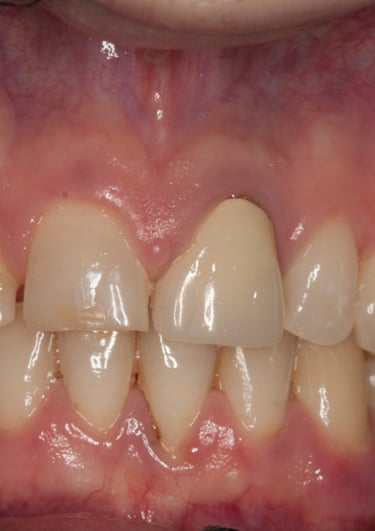

Corona Incongrua

Condizioni Iniziali

Corona Estetica

Condizioni Finali